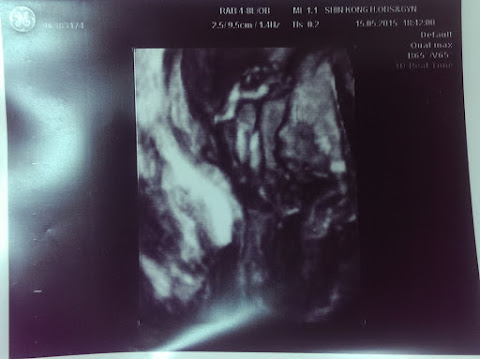

醫生問診完,就拿單子到超音波室排隊等醫生過來照超音波。

小蘋果大小一切正常,正在玩腳趾頭...蕭醫師趁機拍下來給小瑰跟阿童留念。